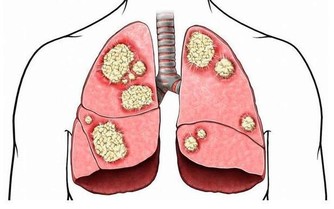

當身體中的濕氣過重時,人就會感覺到全身都不舒服,不是覺得這裡痛,就是那裡酸,沒有辦法專心去做一件事情,會嚴重影響到我們的生活與學習。而且,當身體的濕氣累積到一定程度的時候,身體就會產生各種各樣的毛病。而夏天又是一個濕氣增長的季節,因此,今天我們就來跟大家談一談怎樣趕走我們身體內部的濕氣。

一種最簡單的方法就看看自己長的痘痘多不多。其次,結合臉色情況進行判定。一個人,如果臉上跟背部的痘痘都比較多,而且臉色暗黃,皮膚無彈性,暗淡無光,有一種營養不良的感覺,那就說明很有可能身體濕氣過重。